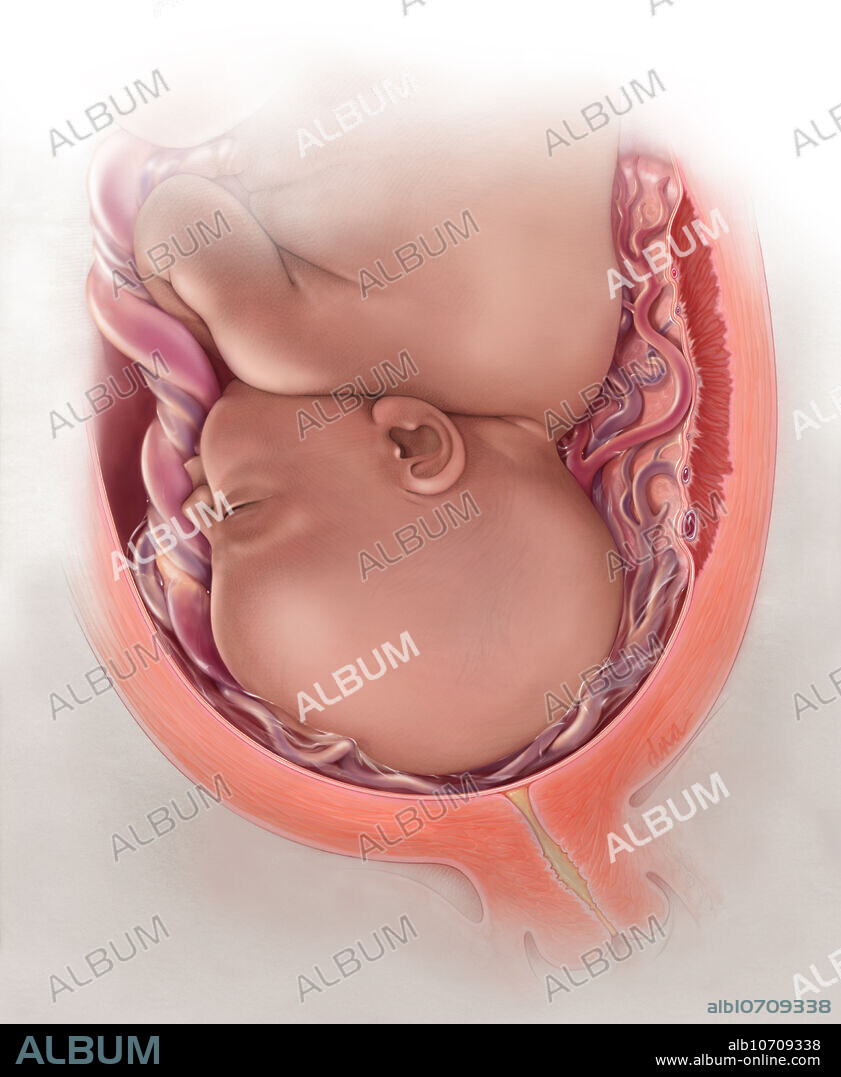

Placenta Model - Taj Scientific Online Store。PVC ZX-1703 Full Term Fetus with Viscera and Placenta at。Mid-trimester sonographic placenta previa thickness and。ペンダーリン シングルカスク ピーテッド。Normal appearance of the anterior placenta: homogeneous。Fetal Growth Restriction: Placental Basis and Implications。。ZX-1700PN Human Placenta Model with Cord at ₹ 5500/piece。Keepsake Items – Midwest Placenta Encapsulation。Placenta Encapsulation - Woven Birth Services。Fetus Baby with placenta 3D Model $25 - .max .unknown .obj。Placenta Encapsulation Training | Lancaster Placenta。Anterior Placenta Labor | TikTok。placentaink on paper201638×40S:54cm×67cm水子の主体に転移して書いた絵です。Anterior/Posterior Placenta? | BabyCenter。